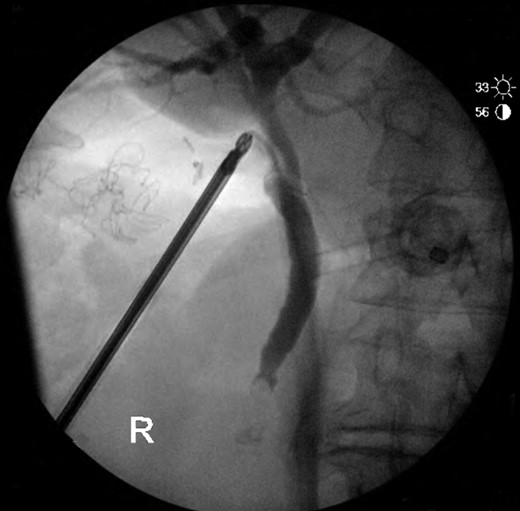

On laparoscopy, the gallbladder could not be identified on exploration of the liver bed. The principle of safe dissection, above axis of the sulcus of Rouviere, was followed to identify landmarks. MRCP imaging was reviewed again intra-operatively to help guide the surgical team and avoid commencing the dissection too low, given that a gallbladder was not present in the fossa. A 2 cm cystic duct stump and cystic artery was identified (Fig. 2). An intra-operative cholangiogram was performed, confirming a distal CBD filling defect (Fig. 3). CBD clearance under direct vision with choledochoscopy was performed to extract a 7 mm stone. The cystic duct was then secured with two PDS Endoloop® Ligatures and sent for histology. A drain tube was placed along the liver bed.

Intra-operative cholangiogram with filling defect in distal CBD.